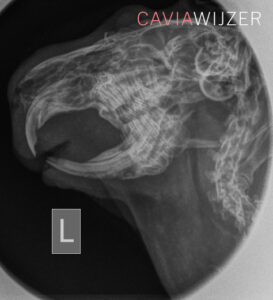

Een caviadierenarts doet bij iedere controle een gebitsinfectie met behulp van een otoscoop. Dit is een medisch instrument waarmee artsen normaal gesproken de binnenkant van het oor bekijken. Het is ook geschikt om het caviagebit te inspecteren op afwijkingen. De cavia hoeft hiervoor niet onder narcose. Helaas zijn niet alle gebitsafwijkingen op deze manier te zien. Voor het opsporen van problemen in de kaak of kieswortels is een röntgenfoto noodzakelijk. Ook hiervoor hoeft de cavia niet onder narcose. Het beoordelen van röntgenfoto’s op gebitsafwijkingen vraagt enige oefening. Een dierenarts met minder ervaring kan de röntgenfoto en/of de cavia eventueel doorsturen naar een meer ervaren dierenarts of een gebitsspecialist.

Wat is er te zien op de röntgenfoto?